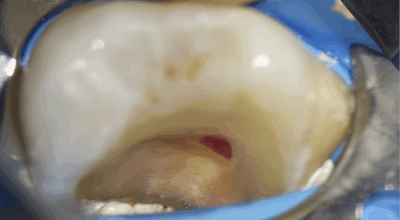

Clinical case

Partial pulpotomy: 88.2% success rate